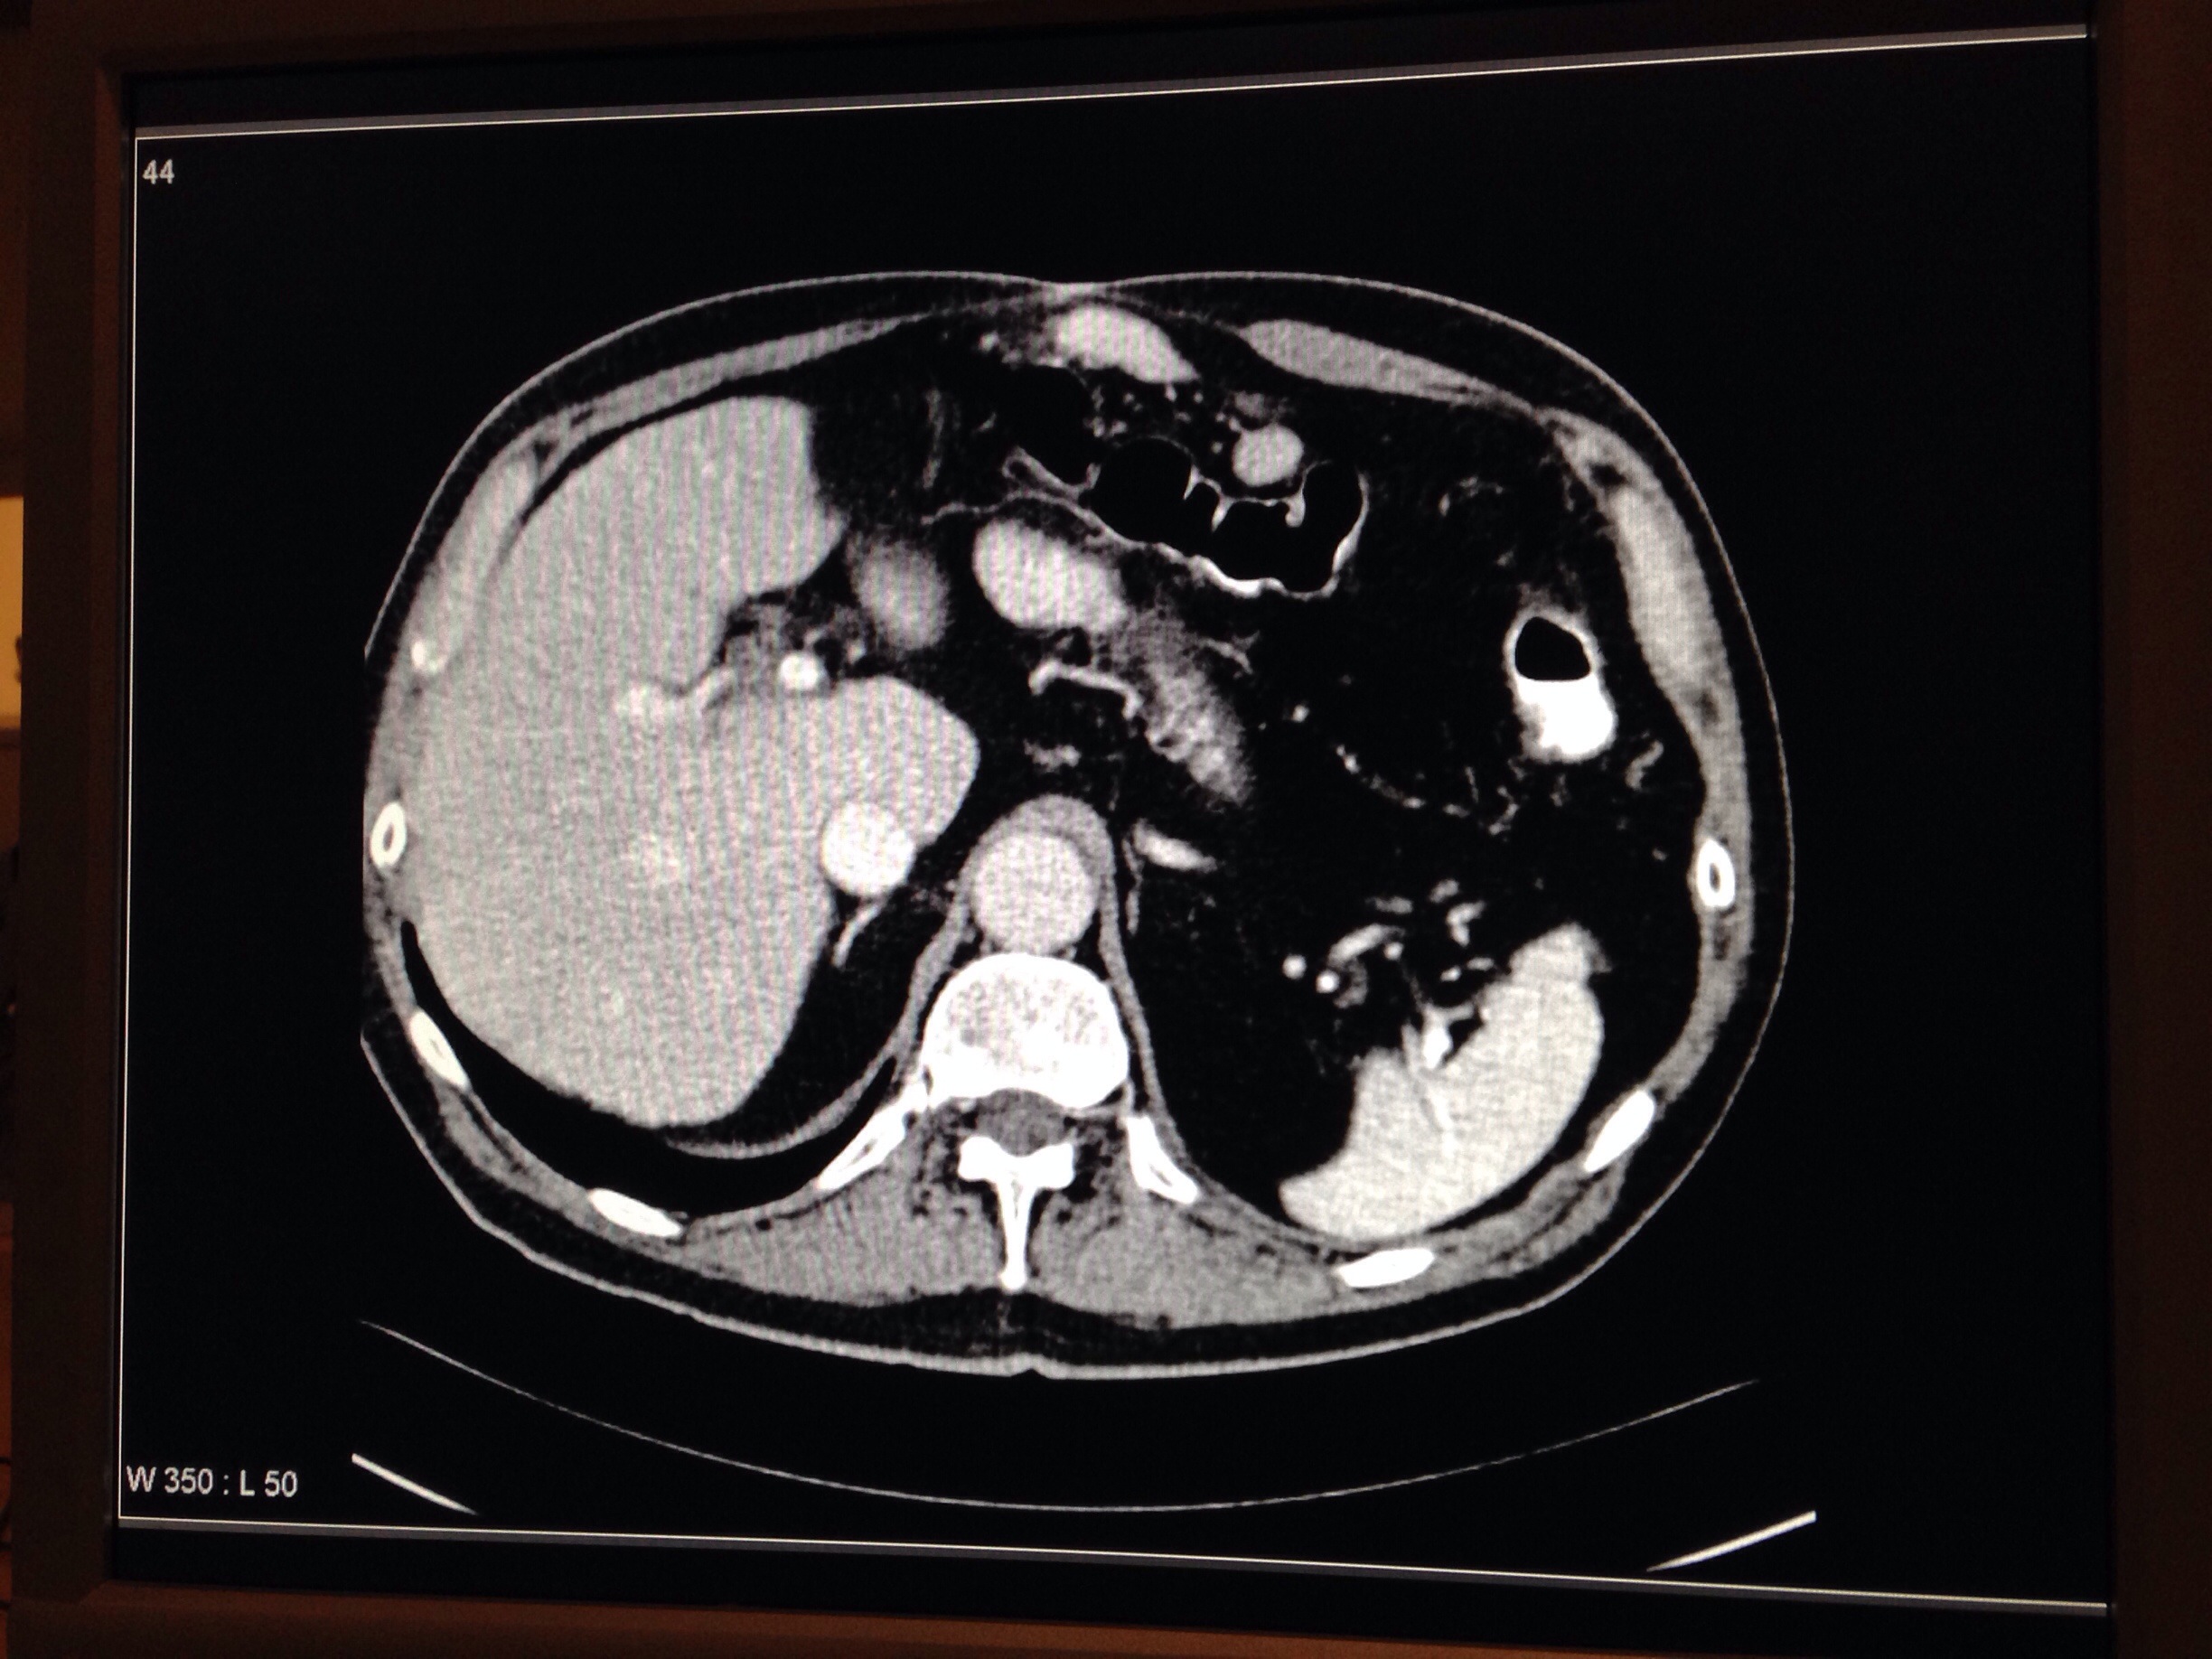

I onsdags var vi nere på sjukhuset och satt en hel eftermiddag och tittade på röntgenbilder, lärde oss massa anatomiska lägen och latinska uttryck för hur man ska beskriva relationen mellan organen i kroppen, samt att överhuvudtaget kunna känna igen de olika delarna 🙂

Här kan vi exempelvis se aorta, vena cava, levern, en bit av pancreas, binjurarna, lungsäcken och mjälten 🙂 Intressant va?! 🙂